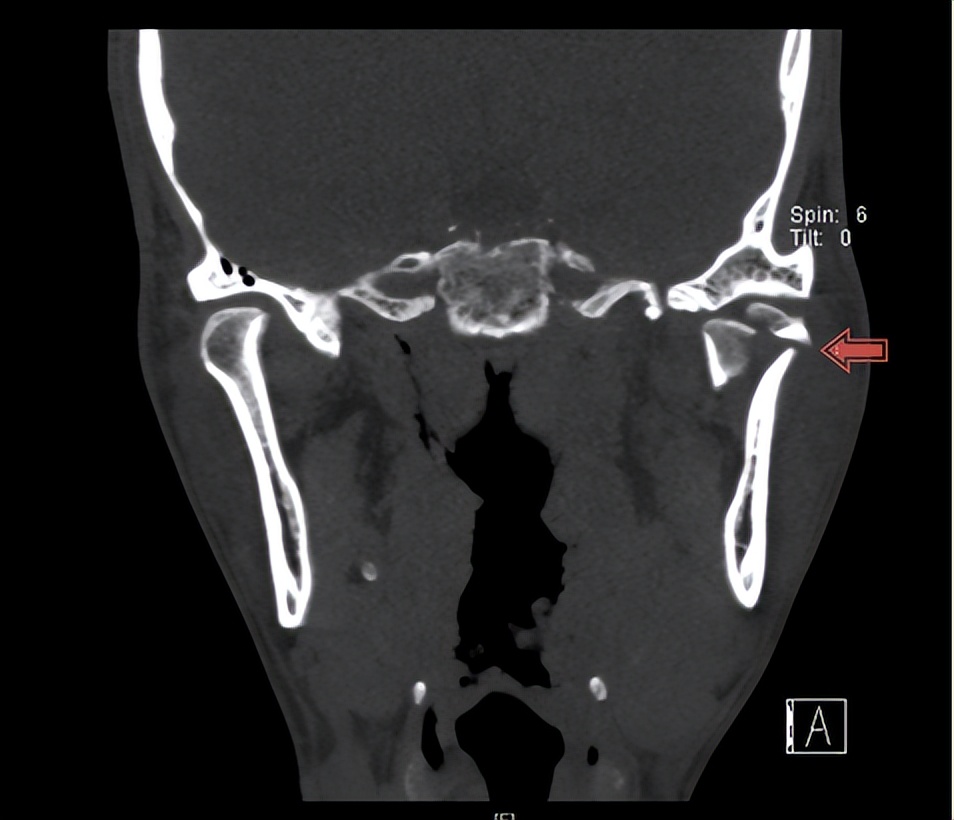

小张前段时间去浴室洗澡,不小心摔了一跤,下巴着地后导致皮肤开裂,深达骨面。身边朋友看小张受伤了,赶紧送往当地医院治疗,医生给小张缝合了下巴创口,让他一周以后到医院拆线。小张回家后,感觉嘴巴和以前不一样了,嘴巴张不大,而且吃饭咀嚼无力。因在苏州工作原因,小张没有在家乡的医院拆线,来我院口腔科就诊,医生拆线后发现,小张咬合关系不佳,建议做颌面部CT检查,检查后发现其左侧髁突粉碎性骨折,需要住院治疗。期间,为小张进行了牵引钉植入并且给予颌间牵引外固定治疗,一周后,小张顺利出院了。

下巴着地会导致髁突骨折?苏州高新区人民医院口腔科主任刘廷忠介绍,髁突是下颌骨的组成部分,其参与构成颞下颌关节的骨突。由于此部位是高应力集中区,且结构比较薄弱,因此很容易发生骨折。临床上,相比于直接受到打击,髁突骨折更常见于间接性应力传导,即下颏(也称为下巴颏)首先受到外力作用,之后再将力传导到髁突颈部或者髁突区域,进而造成髁突骨折。